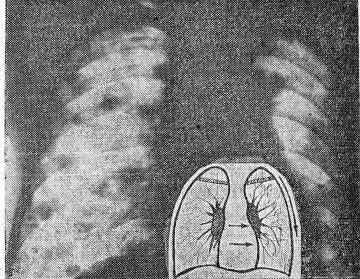

Нередко единственным признаком, заставляющим сомневаться в специфической этиологии процесса, было преимущественное расположение очагов в средних и нижних отделах. Однако явное увеличение не только числа, но и размеров очагов в апико-каудальном направлении мы наблюдали лишь у 9 больных с крупноочаговым карциноматозом, в то время как при милиарном и мелкоочаговом варианте этот симптом отсутствовал или был сомнительным. С другой стороны, известно, что при аналогичных свежих формах диссеминированного туберкулеза очаги на обзорных рентгенограммах также могут быть видны преимущественно в средних и нижних отделах. По нашим наблюдениям, томографическое исследование в этих случаях часто дает обратную картину — увеличение размеров и количества очагов в верхних легочных полях, иногда с тенденцией к слиянию и даже с участками деструкции, что не характерно для карциноматоза (рис. 3, 4).

Рис. 3. Рентгенограмма больного X., 52 лет

Рис. 4. Томограмма больного X., 52 лет

Таким образом, оценку такого важного дифференциально-диагностического признака, как преимущественное расположение очагов при легочных диссеминациях, необходимо проводить в основном с учетом томографических данных.